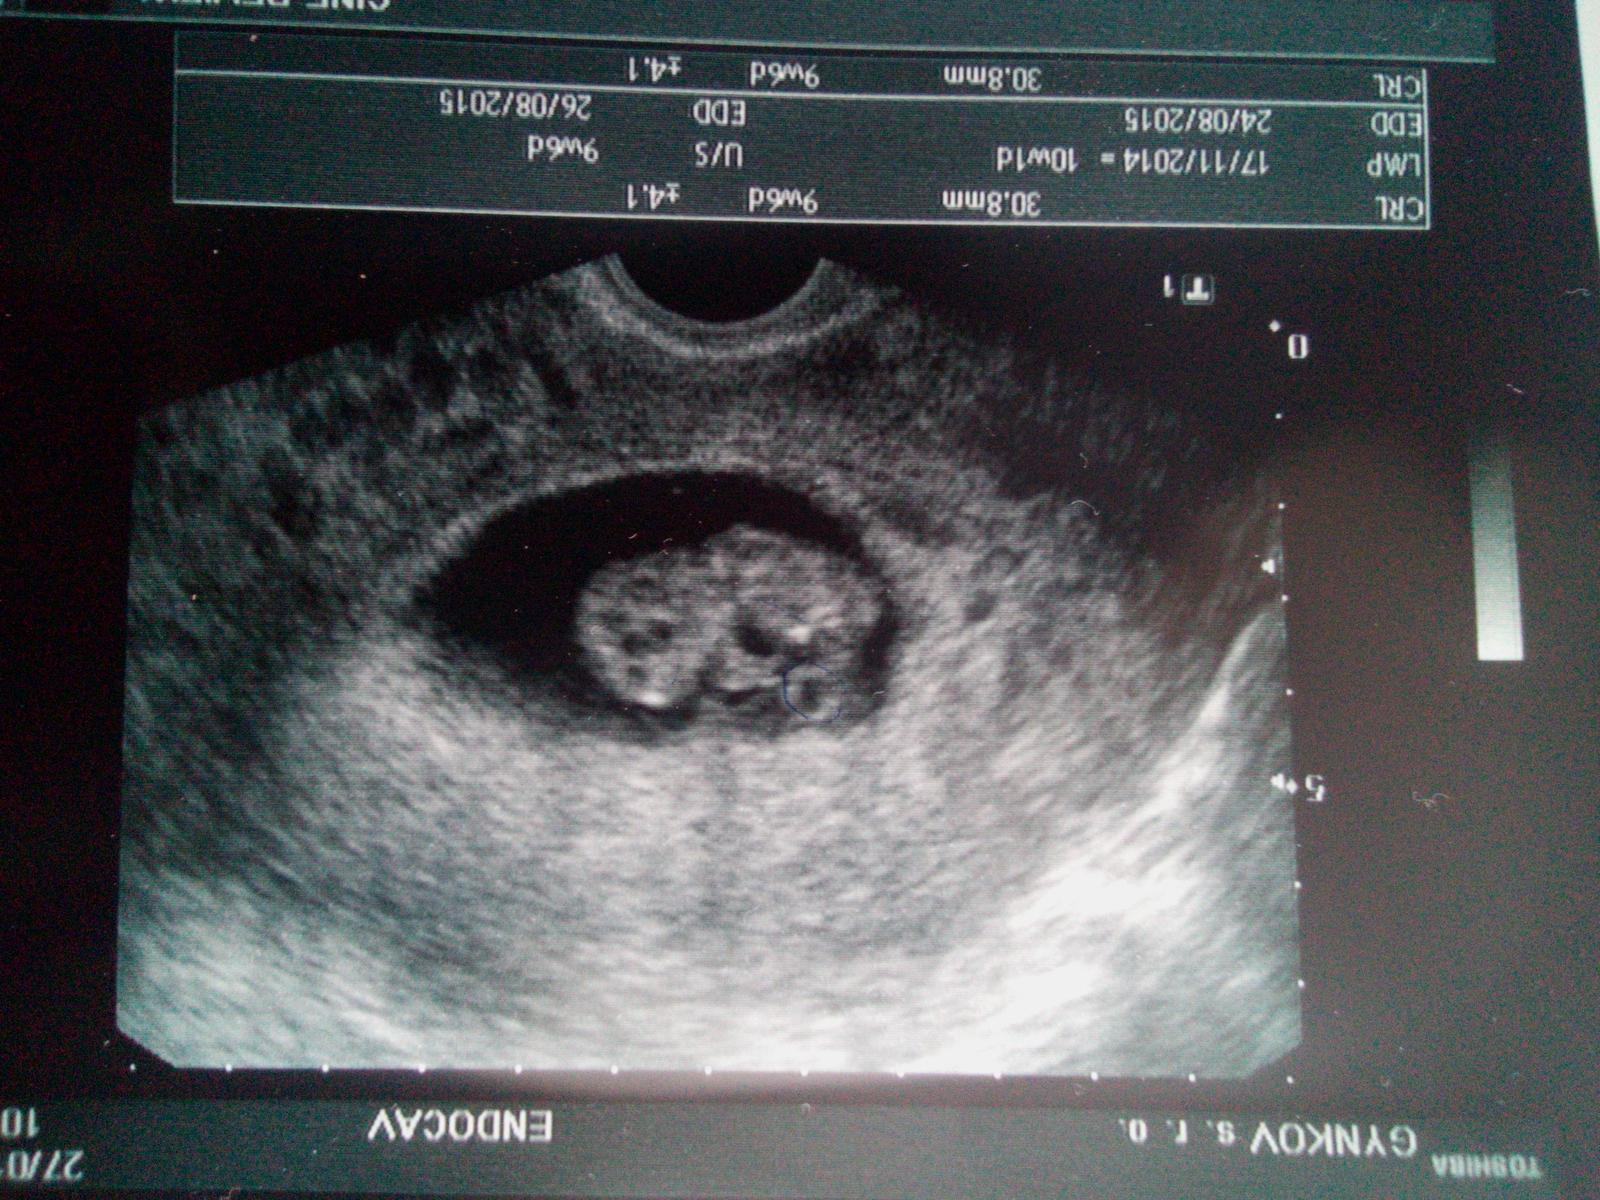

Tak se tedy chlubim.. 😉 Mame 3cm,pry tak akorát,je tam jen jedno-z hrozicich dvou a co se nevolnosti tyce tak pry doktorka je mela do 16tt,takze pry nemusim plasit,ze uz to trva moc dlouho..Jsem zvedava jak dam pristi tyden tu ko na lacno...Odvezu deti a pojedu rovnou tak snad to ustojim a nebudu muset stavet.. 😝

Jezis ja jsem pako,mam tu fotku obracene.. ☹

@veraakubik Kráááásné 🙂 Takže je miminko teda jedno ju? 🙂 To je krááásné,já se tak těším na zítra,až ho taky uvidím,snad bude vše ok

@ronyx jj,jedno..Docela mi spadl kamen ze srdce.. 😉 Urcite bude všechno v poradku a zítra se nam pochlubis ty!Drzim palecky!